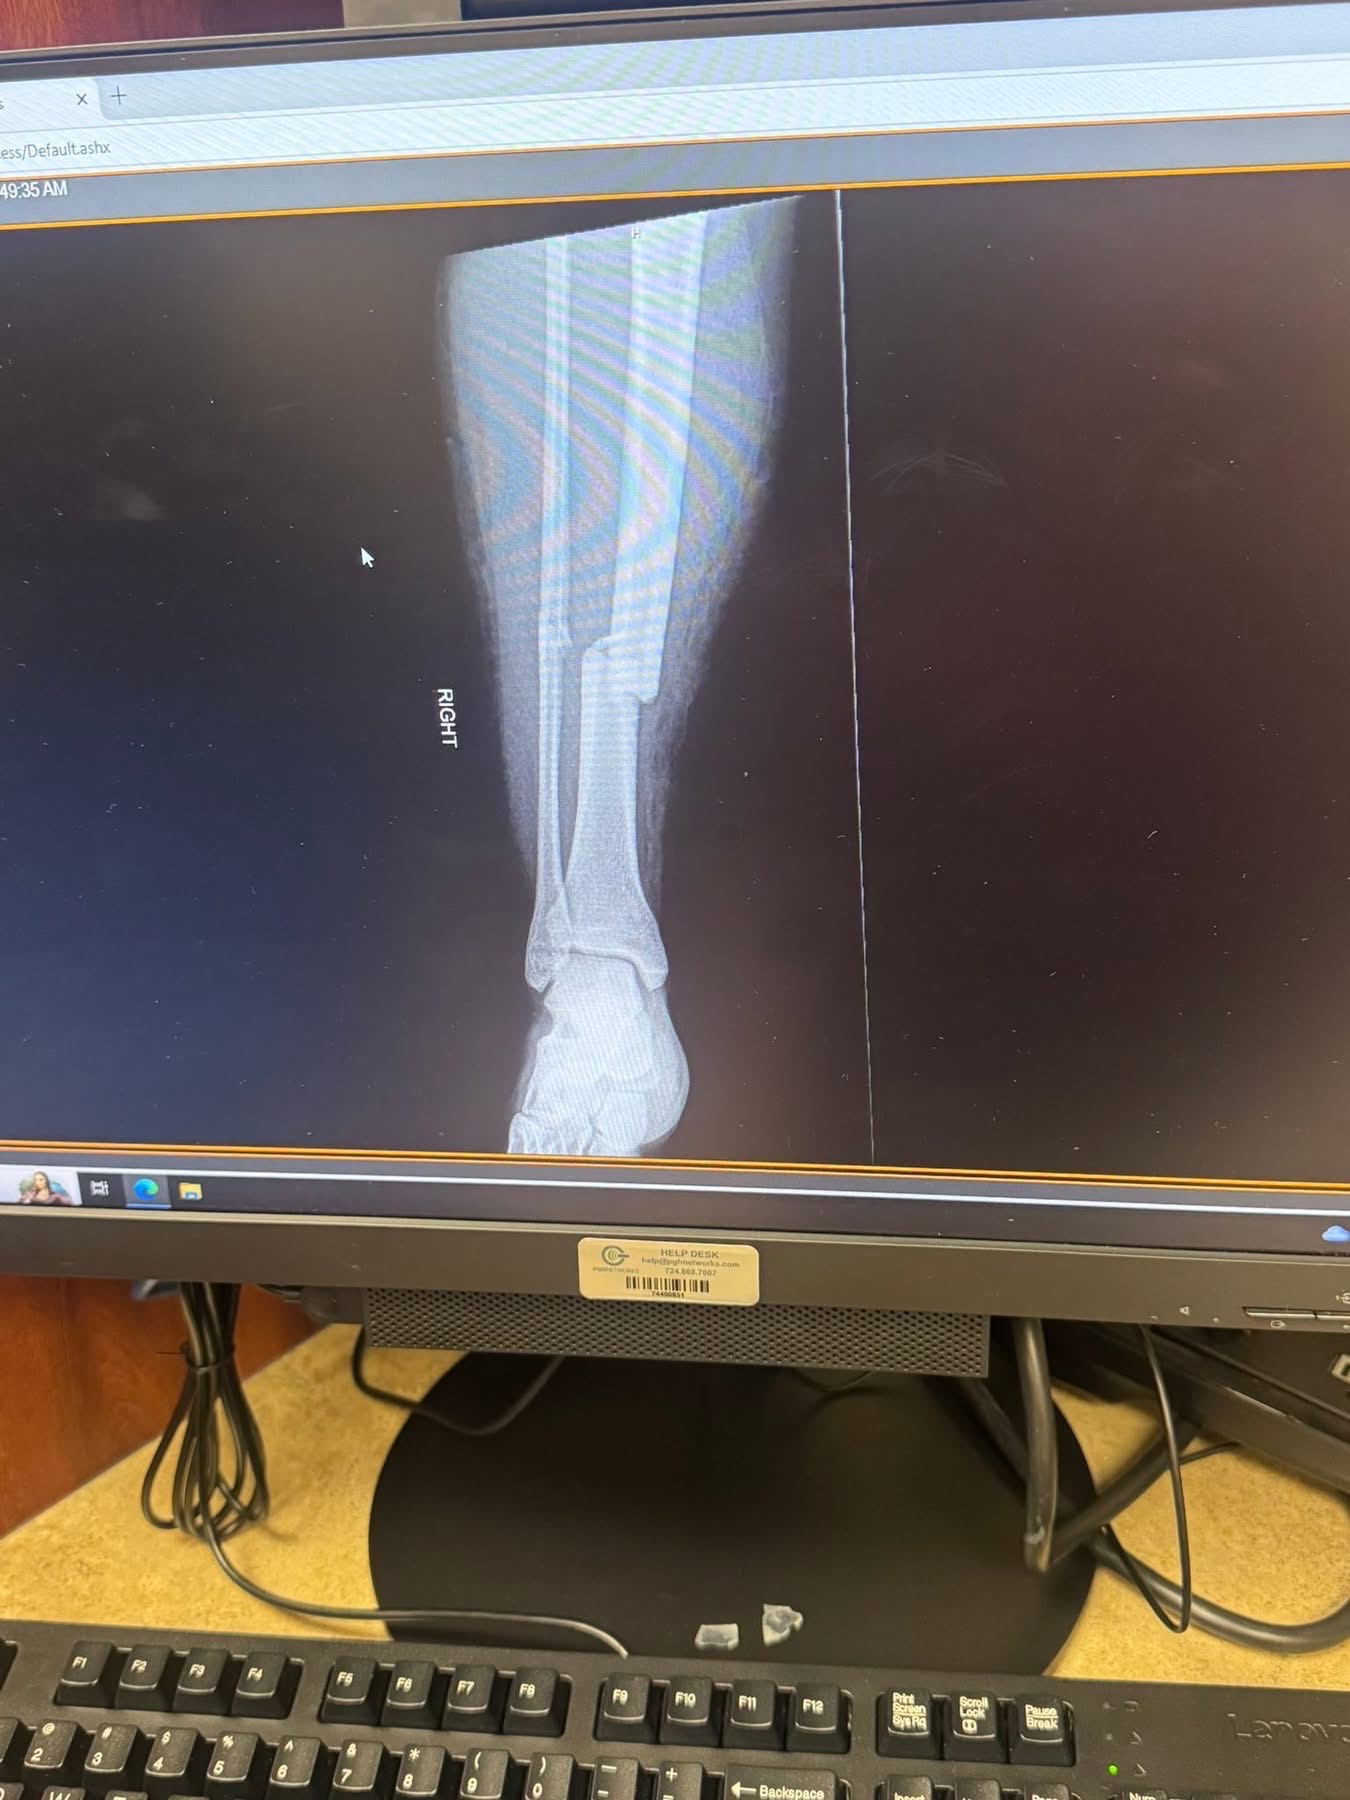

Just a little update. Logan is home he’s doing good they ended up putting 2 nails and 5 screws in his leg. His job is going to give him a desk job until he’s better and the doctor said after about a month of rehab he should be good to go back to work even though at first it will just be working in the office. Then overall probably a little over 3 months till he will pretty much be fully good to go. I’m glad that God worked things out and that Logan is doing good. ❤️